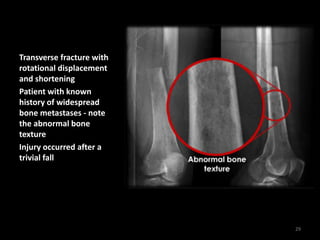

Transverse fracture with

rotational displacement

and shortening

Patient with known

history of widespread

bone metastases - note

the abnormal bone

texture

Injury occurred after a

trivial fall